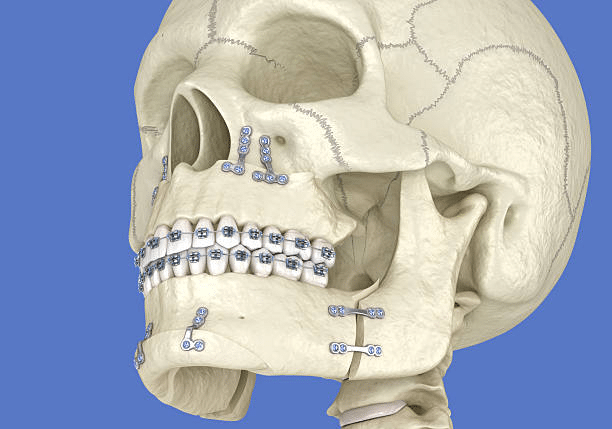

This type of jaw surgery repositions the upper jaw (maxilla). It is performed when the upper jaw protrudes too far forward, sits too far back or has grown unevenly. The surgeon makes cuts above the teeth, moves the jaw into the correct position and secures it with titanium plates and screws. Conditions treated include a significant open bite, crossbite and certain types of overbite.

Lower jaw surgery corrects a mandible that extends too far forward or too far back. The surgeon makes incisions behind the molars, repositions the lower jaw and fixes it in place with surgical hardware. This is one of the most common jaw surgery basics and is frequently recommended for patients with a severe underbite or receding lower jaw.

When both the upper and lower jaws require correction, a bimaxillary osteotomy is performed. This is the most complex type of jaw surgery, repositioning both jaws during a single operation. According to the University of Utah Health, double jaw surgery is also used to treat obstructive sleep apnoea by advancing both jaws to open the airway.

1. Pre-Surgical Phase

Before jaw surgery, patients undergo orthodontic treatment to move the teeth into positions that will align correctly once the jaw is repositioned. This phase typically lasts 12 to 18 months and involves wearing braces or aligners. The orthodontist and surgeon work together using 3D scans, X-rays and digital imaging to plan the precise surgical movements.

- The surgeon makes incisions inside the mouth to access the jawbone, minimising visible scarring.

- Precise cuts are made in the bone to allow the jaw to be moved into the planned position.

- Bone may be added, removed or reshaped as needed.

- The jaw is secured in its new position using titanium plates, screws or wires.

- Incisions are closed and a splint may be placed over the teeth for stability.